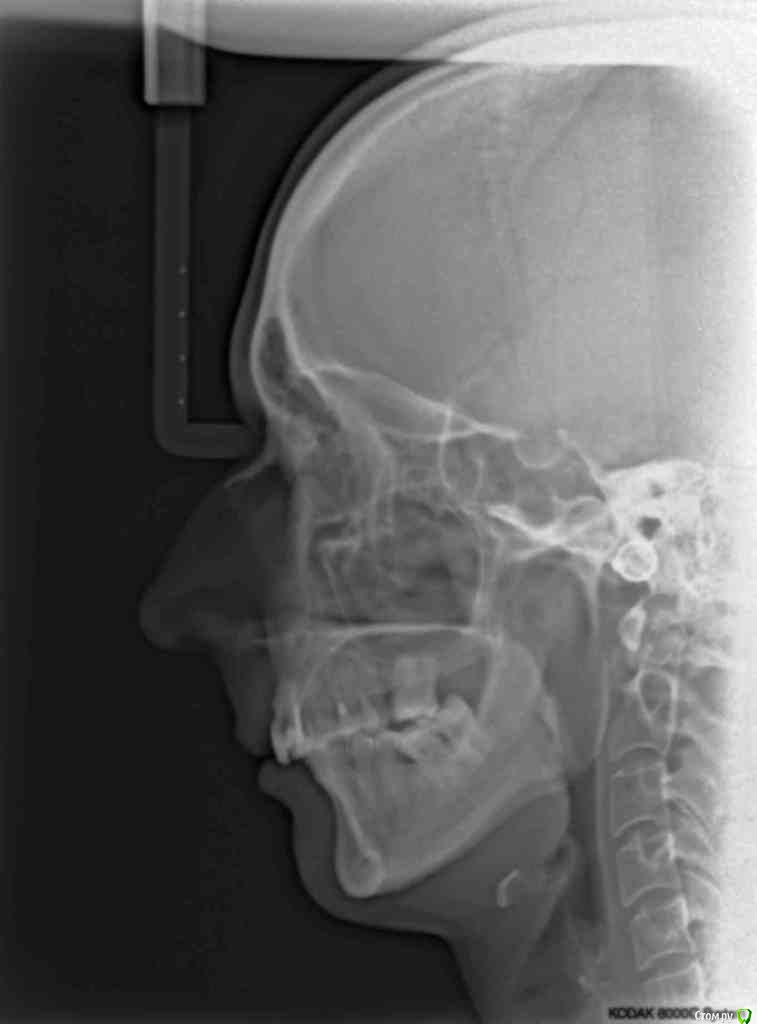

VVQW Опубликовано 25 октября, 2016 Поделиться Опубликовано 25 октября, 2016 (изменено) добрый день. Сложная ситуация. Более 10 лет назад ставили брекеты без анализов, диагностик, снимков и пр. Сейчас, что имееем, то и имеем. Большую проблему. Прикуса нет. Клиновидки из-за перегруза. Что можно сделать прошу совета и помощи. Обращалась за консультацией ко многим специалистам, мнения разнятся от слегка положительного, до просто критической ситуации. Последний профессор ортодонт вообще сказал - все вырвать и поставить протезы. УЖАС..... Может кто-нибудь из врачей даст совет... очень на Вас надеюсь. С уважением. Изменено 25 октября, 2016 пользователем VVQW Ссылка на комментарий

VVQW Опубликовано 6 декабря, 2016 Автор Поделиться Опубликовано 6 декабря, 2016 (изменено) Лечение скорее всего будет неким компромисом. Я правильно понимаю, 10 лет назад сняли брекеты?Брекеты были сняты более 10 лет назад. Ретейнеры не ставились. Верхние 6-ки по решению врача были убраны для задвигания зубов к заду, верхние 8-ки - не выросли. Нижние 6-ки - удалены в подростковом возрасте, до 14 лет. http://s019.radikal.ru/i641/1612/eb/3498e6cec3f8.jpg http://s018.radikal.ru/i518/1612/73/739600b6d2d1.jpg http://s011.radikal.ru/i318/1612/73/443e1513aaf8.jpg http://s017.radikal.ru/i403/1612/86/73e0dfe4ca62.jpg http://s018.radikal.ru/i518/1612/a2/bd7078537d9e.jpg http://s017.radikal.ru/i417/1612/9d/41b6d1c98666.jpg http://s019.radikal.ru/i642/1612/fe/3222fa19d517.jpg Гипсовых моделей нет, зубы неподвижны. http://s019.radikal.ru/i639/1612/56/1345f17db908.jpg http://s019.radikal.ru/i630/1612/55/145ef7c813b2.jpg http://s017.radikal.ru/i440/1612/c2/74bd4da2643e.jpg http://s008.radikal.ru/i303/1612/b4/e80683ed7d2b.jpg http://s010.radikal.ru/i314/1612/74/6d2f9671b0d5.jpg http://s018.radikal.ru/i502/1612/97/9a15fcf4ddd3.jpg http://s020.radikal.ru/i715/1612/59/9bb4a006621f.jpg Изменено 6 декабря, 2016 пользователем VVQW Ссылка на комментарий

VVQW Опубликовано 6 декабря, 2016 Автор Поделиться Опубликовано 6 декабря, 2016 Брекеты были сняты более 10 лет назад. Ретейнеры не ставились. Верхние 6-ки по решению врача были убраны для задвигания зубов к заду, верхние 8-ки - не выросли. Нижние 6-ки - удалены в подростковом возрасте, до 14 лет.зубы неподвижны. Ссылка на комментарий

Brigita Опубликовано 6 декабря, 2016 Поделиться Опубликовано 6 декабря, 2016 (изменено) У Вас сложный случай, но лечение было бы возможным, если бы не резорбция корней верхней челюсти. Ортодонт принимая решение о лечении такого пациента должен понимать, что он берет на себя большую юридическую ответственность. Я думаю, все это Вам уже говорили. Ищите опытного врача и будьте готовы к вложению средств и потерям зубов... Скорее всего имплантация неизбежна и фронтального и частично бокового отдела.Сколько Вам лет? Изменено 6 декабря, 2016 пользователем Brigita Ссылка на комментарий